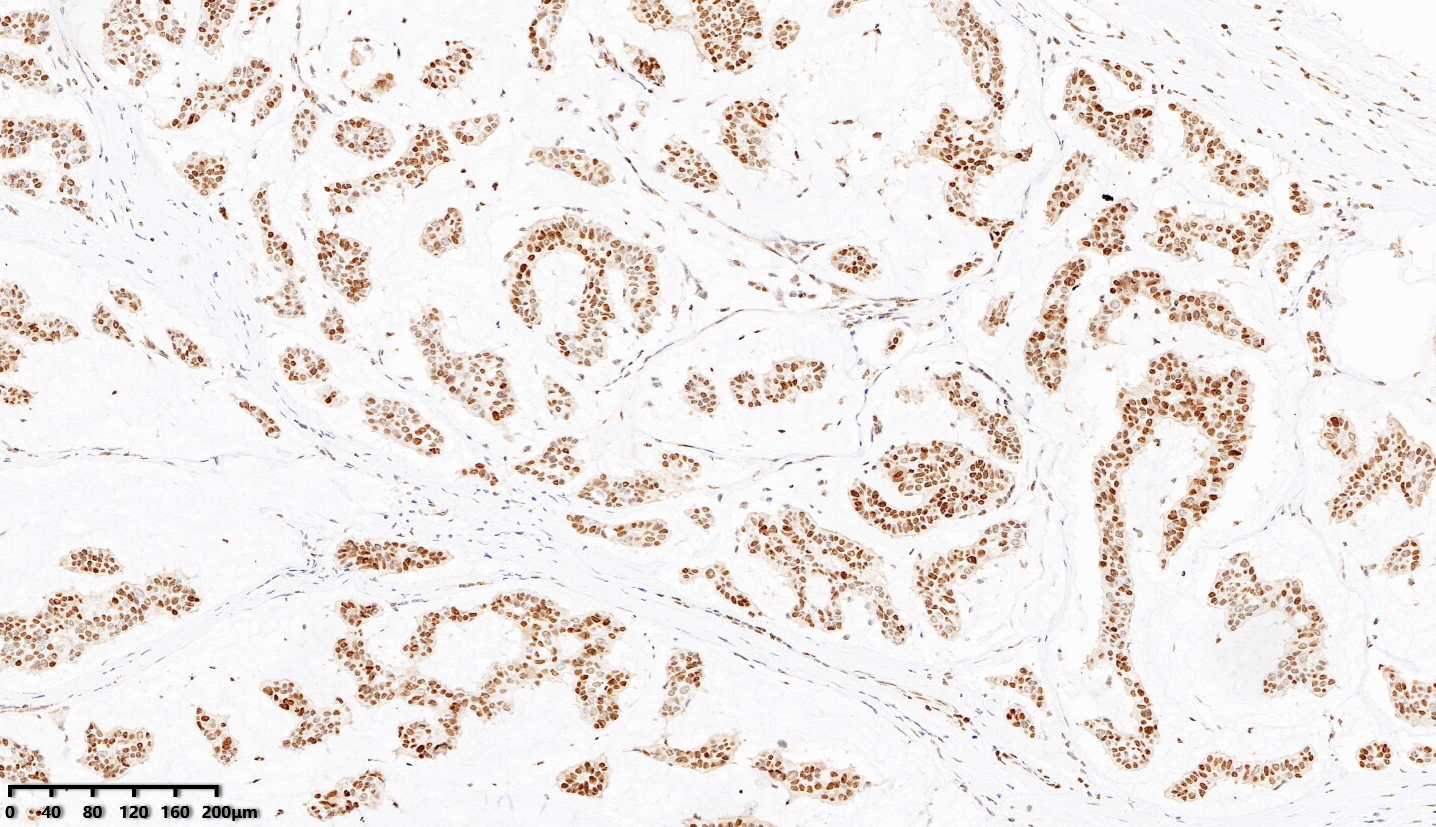

【新品單抗】BRCA1

單克隆兔抗人BRCA1

BRCA1定位于染色體17q21,共22個外顯子,編碼1863個氨基酸的磷酸蛋白,參與BRCA1相關基因組監視復合體(BASC),與修復DNA雙鏈斷裂相關,是一種腫瘤抑制基因。BRCA1基因的突變與遺傳性乳腺癌/卵巢癌相關,并可累及其他器官,為一組癌癥易感性增高疾病,發病率約1/1000~1/500。約5%的乳腺癌患者發現有BRCA1或BRCA2基因的突變。BRCA1基因的突變或啟動子高甲基化可導致BRCA1蛋白抑癌功能的缺陷或表達缺失。

| 克隆號 | 定位 | 陽性對照 | 修復條件 |

| EPR19433 | 細胞漿/細胞核 | 乳腺癌 | 高PH熱修復 |

乳腺癌,BRCA1染色,DAB顯色